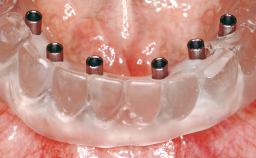

Conventional Loading of Eight Implants in the Maxilla and Final Restoration with a Full-Arch Gold-Ceramic FDP

Prosthesis Type FDP

Defining Characteristics Fully edentulous upper jaw to be rehabilitated with an implant-borne fixed dental prosthesis

Loading Protocol Conventional or early

Retention Cemented, with prosthesis margin < 3mm submucosal Cemented, with prosthesis margin < 3mm submucosal

Provisional Implant-Supported Prosthesis Prosthodontic margin < 3 mm apical to mucosal crest Prosthodontic margin < 3 mm apical to mucosal crest

Interim Prosthesis during Healing Removable Removable